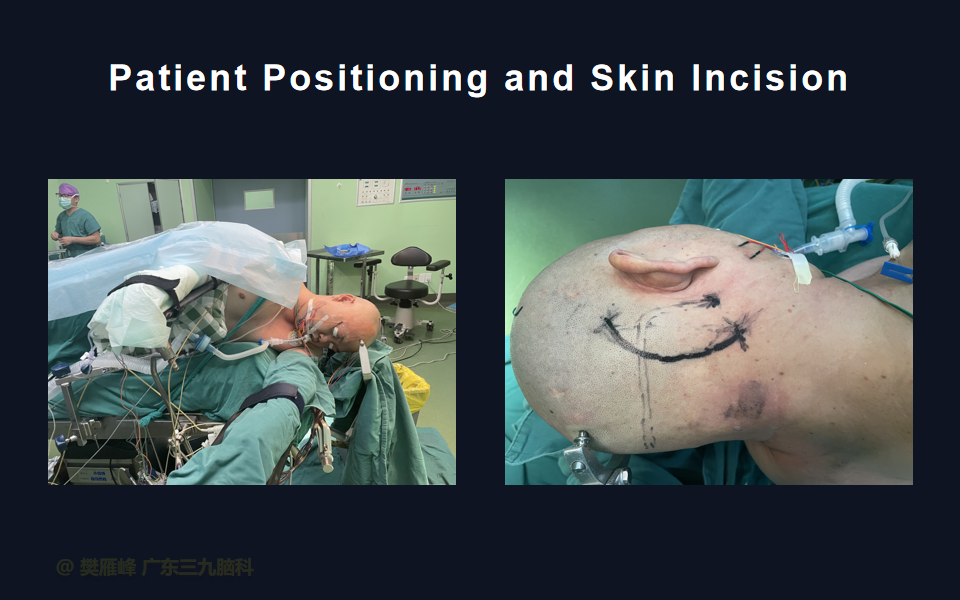

在这个二维手术视频中,展示了一种经枕下乙状窦后入路束膜下分离保留面神经的方法。患者是一名51岁的男性,有1年右耳听力下降伴耳鸣、无步态不平衡病史,术前有右侧轻度面瘫,神经影像学显示右侧桥小脑角区约30×30×29mm的囊实性占位,增强后实性部分及囊壁可见明显强化。他接受了经乙状窦后入路保留面神经的方法,术中肿瘤全切除,面神经被肿瘤挤压成薄膜状覆盖于三叉神经表面。术后面瘫加重,听力未能保留,神经影像学显示肿瘤全部切除。我们展示了安全的颅神经保护和肿瘤切除的细微差别和技术要点,以及手术技术。